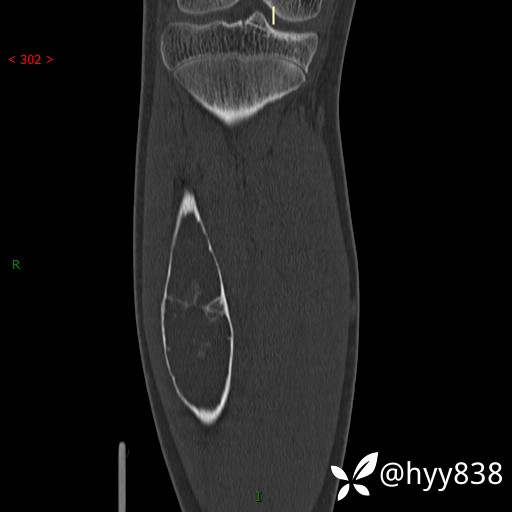

SAG

儿童,发现右小腿肿硬性肿物3年。资料齐全,ABC VS SBC VS FD--结果公布

临床诊断:胫骨肿物